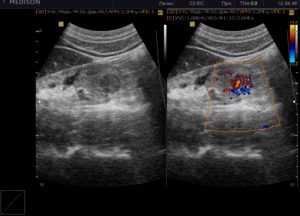

При подозрении на злокачественное образование специалист будет внимательно отслеживать эхогенность нужных участков органа

При подозрении на злокачественное образование специалист будет внимательно отслеживать эхогенность нужных участков органа. Как правило, онкология на УЗИ имеет такие проявления:

- Небольшое образование гипоэхогенно.

- Крупное образование гиперэхогенно.

- Для опухоли характерна смешанная эхогенность из-за структурных изменений в тканях почек.

- Часто специалист может отслеживать изоэхогенность подозрительного участка больного органа. То есть структура образования схожа с окружающей почечной тканью.

Важно: сложно просматриваются на УЗИ злокачественные образования до 1 см в диаметре. При этом даже они имеют ровные и плотные контуры.

- Крупное образование имеет неоднородную структуру и смешанную эхогенность.

- Если онкология давняя, то в зонах распада образования будут просматриваться кисты с жидким содержимым. Такие участки будут совсем черными или тёмно-серыми (видно потемнение) и иметь неправильную форму.

- Все злокачественные образования будут иметь совершенно отличную от паренхиматозной акустическую плотность.

- При наличии онкологии контуры органа могут быть слегка выпяченными.

- Эхо-сигнал чаще прерывистый.

Важно: если проводится доплерография, то при онкологии рисунок сосудов может меняться от полного его отсутствия до чрезмерной васкуляризации при высокой интенсивности цветового сигнала.